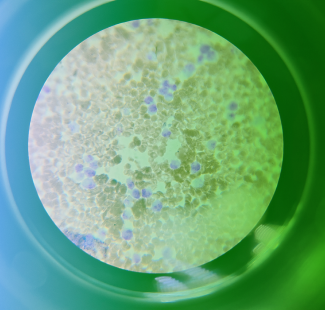

(BRONX, NY)— Researchers at Albert Einstein College of Medicine have developed a topical drug that regenerates and restores the function of erectile nerves damaged by radical prostatectomy, the most common treatment for localized prostate cancer. The drug was tested in rats, and the findings were published online today in JCI Insight. These images show neurons cultured in petri dishes and treated